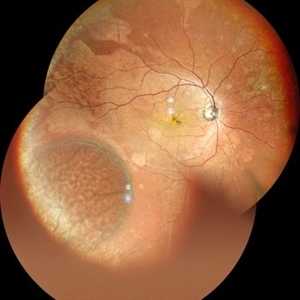

Exudative Retinal Detachment secondary to Leber's Miliary Aneurysm in a case of Retinitis Pigmentosa

Oct 13 2022 by Vaidehi Sathaye

Fundus Photograph of RE of a 23 year male patient , with an Exudative Retinal Detachment secondary to Leber's Miliary Aneurysm in a case of Retinitis Pigmentosa.

Photographer: Dr. Vaidehi Sathaye

Imaging device: Mirante

Condition/keywords: exudative detachment, Leber's miliary aneurysm, retinitis pigmentosa